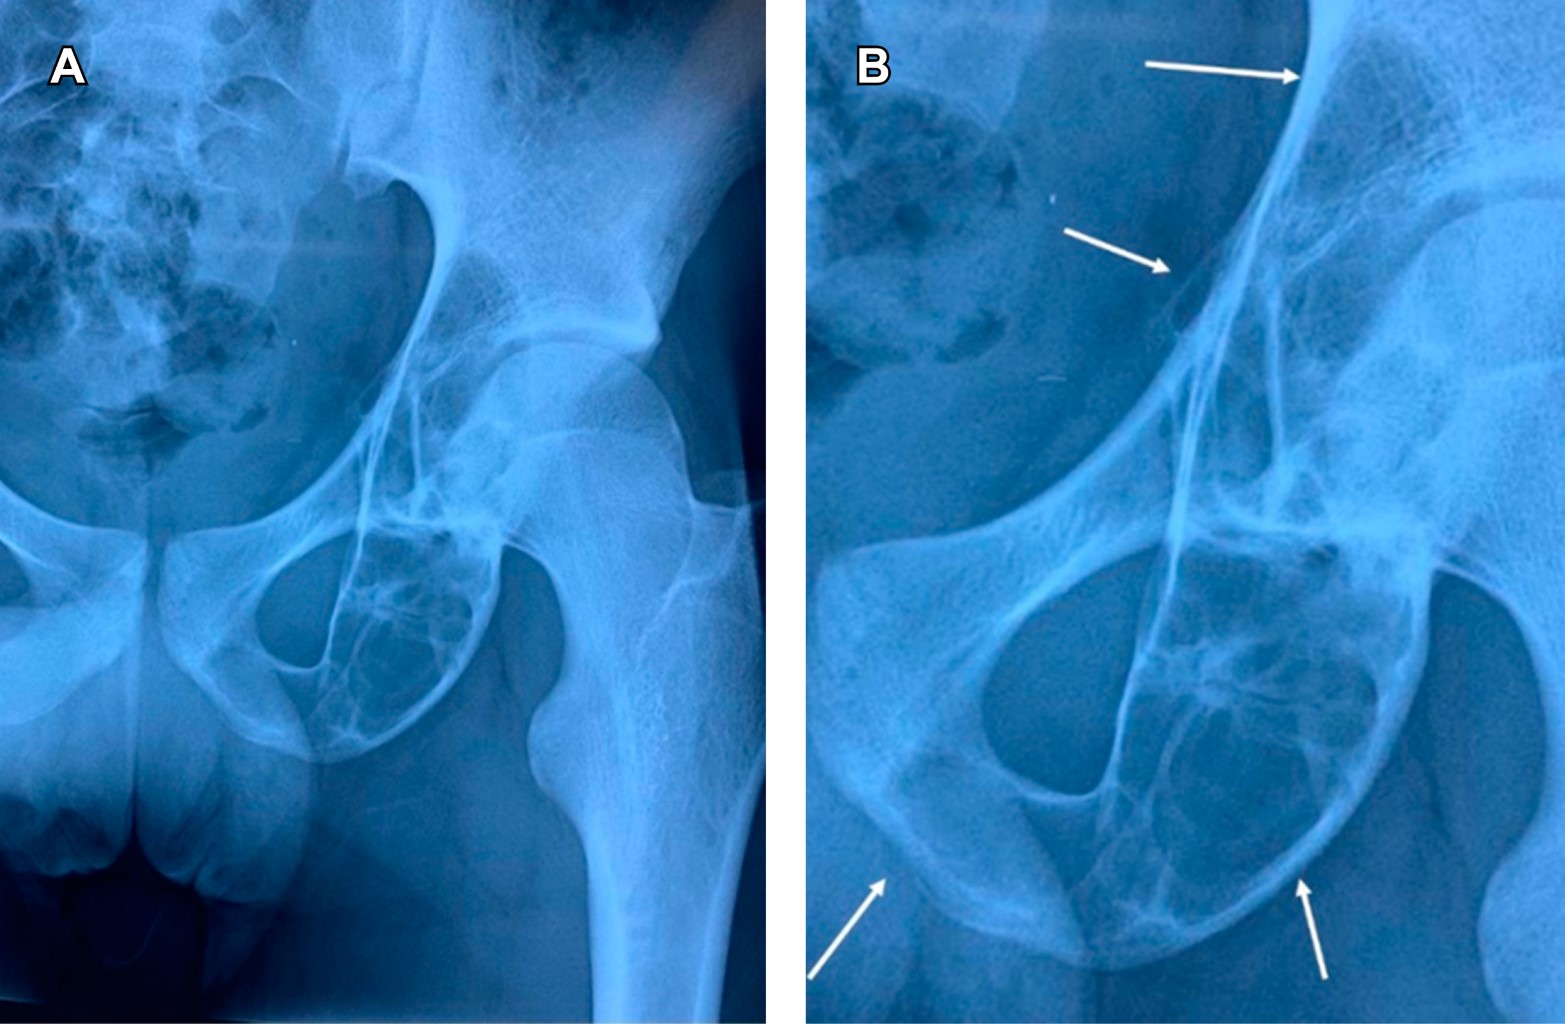

Figure 1